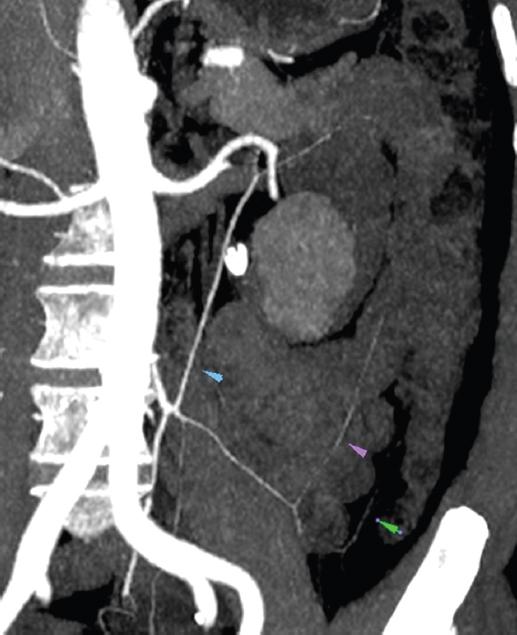

Figure 3 Two dimensional-computed tomography angiography: left to right vascular arcades of Moshkovich, Riolan and Drummond.

Riolan’s arch is an “intermediate” anastomosis between the branches of the SMA and IMA in the mesentery of the colon2,4. In our study, we found the presence of this structure in 47 (45.6%) patients (Figs. 1-3).

The Moshkovich’s artery, also known as the tortuous mesenteric artery, is a lesser-known collateral route and is another link between the SMA and IMA. The Moshkovich’s artery runs along the base of the mesentery of the colon and is the connecting link between the proximal segment of the MCA and the ascending branch of the LCA2,6. In our study, we found the presence of this artery in only 1 (1%) patient (Fig. 2 and 3).